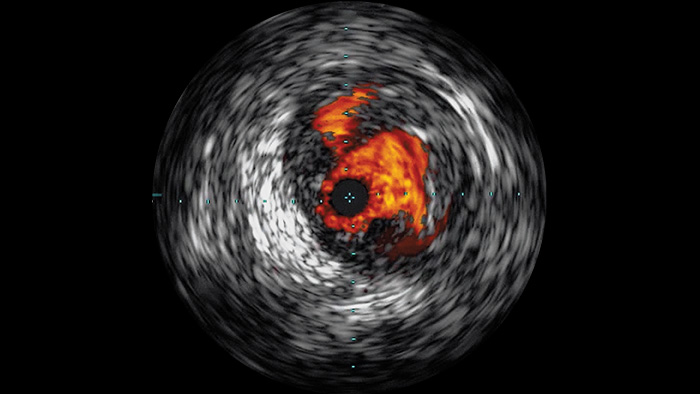

Ecografía intravascular (EIV) mejora la evaluación de la enfermedad

EIV image

La ecografía intravascular (EIV) es una tecnología de imágenes basada en catéteres que permite a los médicos visualizar los vasos sanguíneos de adentro hacia afuera para ayudar a evaluar la presencia y el alcance de la enfermedad. La EIV ayuda a decidir, guiar y confirmar el tratamiento intervencionista adecuado para cada paciente.